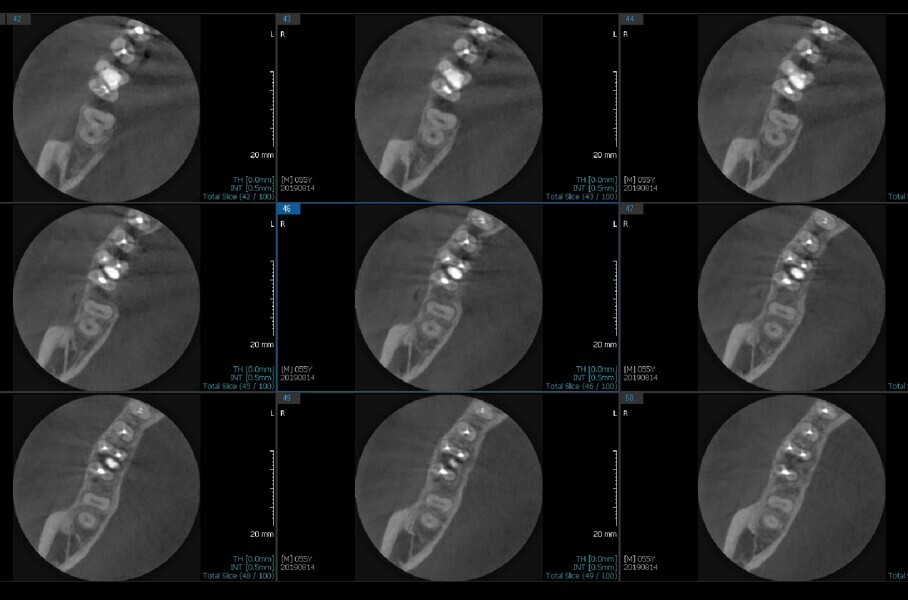

Fig.2a: Pre-op CBCT images of tooth #46: No obturation material in the distal and mesiobuccal canal (a); scanty obturation of the canals and breach of the floor of the pulp chamber, no obturation beyond a few millimetres down the orifice (b & c); radiolucency in the furcation area and periapical region of both roots (d -g).

Fig.2b: Pre-op CBCT images of tooth #46: No obturation material in the distal and mesiobuccal canal (a); scanty obturation of the canals and breach of the floor of the pulp chamber, no obturation beyond a few millimetres down the orifice (b & c); radiolucency in the furcation area and periapical region of both roots (d -g).

Fig.2c: Pre-op CBCT images of tooth #46: No obturation material in the distal and mesiobuccal canal (a); scanty obturation of the canals and breach of the floor of the pulp chamber, no obturation beyond a few millimetres down the orifice (b & c); radiolucency in the furcation area and periapical region of both roots (d -g).

Fig.2d: Pre-op CBCT images of tooth #46: No obturation material in the distal and mesiobuccal canal (a); scanty obturation of the canals and breach of the floor of the pulp chamber, no obturation beyond a few millimetres down the orifice (b & c); radiolucency in the furcation area and periapical region of both roots (d -g).

Fig.2e: Pre-op CBCT images of tooth #46: No obturation material in the distal and mesiobuccal canal (a); scanty obturation of the canals and breach of the floor of the pulp chamber, no obturation beyond a few millimetres down the orifice (b & c); radiolucency in the furcation area and periapical region of both roots (d -g).

Fig.2f: Pre-op CBCT images of tooth #46: No obturation material in the distal and mesiobuccal canal (a); scanty obturation of the canals and breach of the floor of the pulp chamber, no obturation beyond a few millimetres down the orifice (b & c); radiolucency in the furcation area and periapical region of both roots (d -g).

Fig.2g: Pre-op CBCT images of tooth #46: No obturation material in the distal and mesiobuccal canal (a); scanty obturation of the canals and breach of the floor of the pulp chamber, no obturation beyond a few millimetres down the orifice (b & c); radiolucency in the furcation area and periapical region of both roots (d -g).